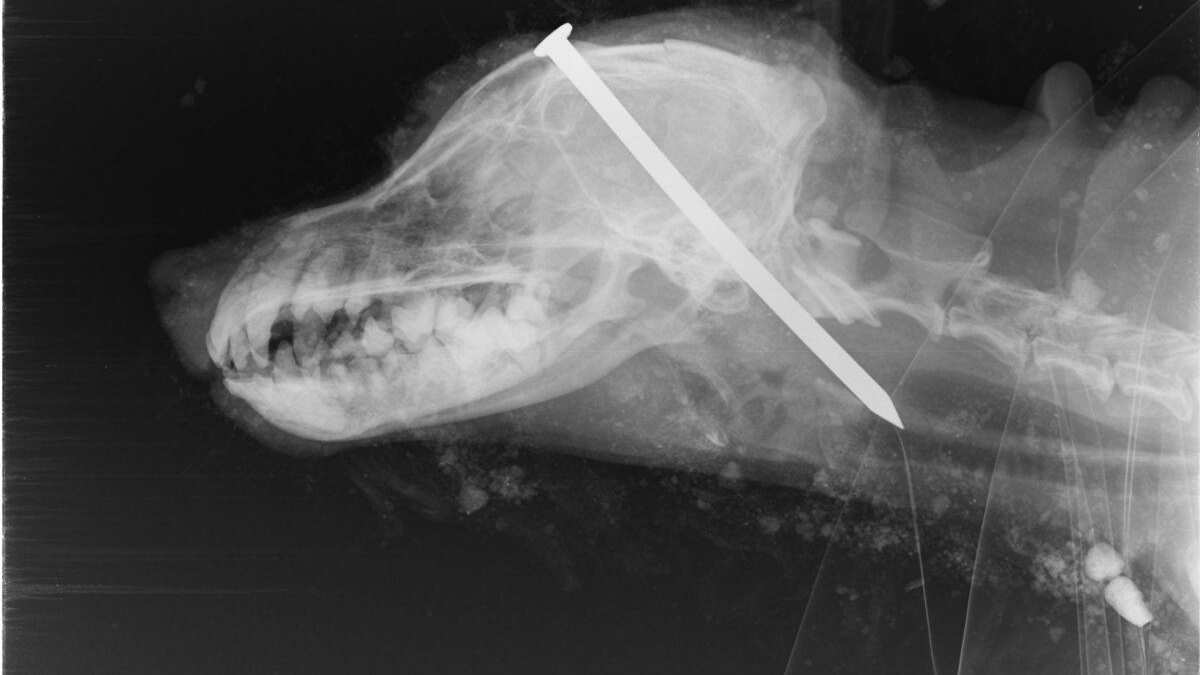

El canino fue trasladado a un hospital veterinario. Estaba en un pésimo estado de salud. Sin embargo, lo más sorprendente fue cuando le tomaron una radiografía de la cabeza y se confirmo que tenía un clavo inscrustado en la parte superior de la cabeza.